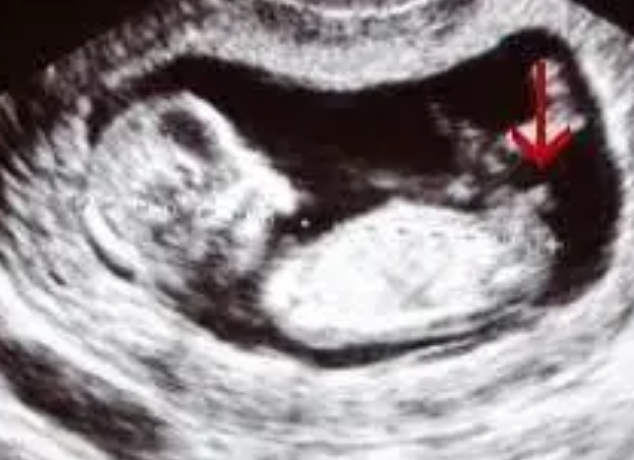

然而,尽管存在以上局限性,B超在男女鉴定中的准确率仍然比较高。研究表明,当胎儿达到12周以上时,B超技术的准确率可以达到90%以上。在20周以上,准确率更高,接近100%。因此,在实际应用中,B超仍然是一种较为可靠的男女鉴定方法。

案例一:一位孕妇在怀孕20周时进行了B超检查,结果显示胎儿为男性。后续的出生证明和其他医学检测结果也证实了这个结果的准确性。

案例二:一对夫妇想要知道胎儿的性别,经过B超检查显示胎儿为女性。后续的产检和出生也证实了这个结果的准确性。

这些案例表明,B超在男女鉴定中的准确率较高,在实际应用中取得了良好的效果。